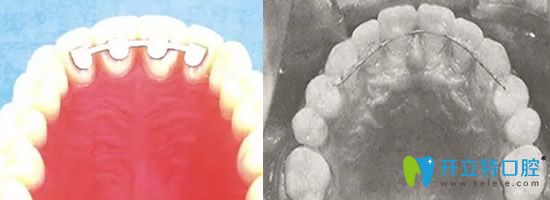

3、第三種局部保持器,是一種其局部保持效果可控的保持器,除了金屬絲的,目前還有纖維帶質(zhì)地的,效果、功能還是美觀度都是比較高的,是目前一種可以大力推廣的保持器。

【優(yōu)點】:非常舒適的,對于矯正效果要求極其高的保持器,對于上述兩種保持器異物感不耐受,尤其是青少年容易將保持器丟失的受者都可以使用這種保持器。

【缺點】:對于粘合劑的要求非常高,目前使用的粘合劑有待改進(jìn)和提高。

局部保持器